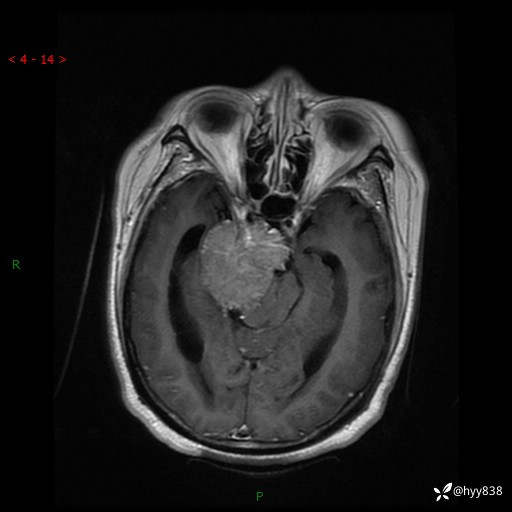

颅脑CT平扫